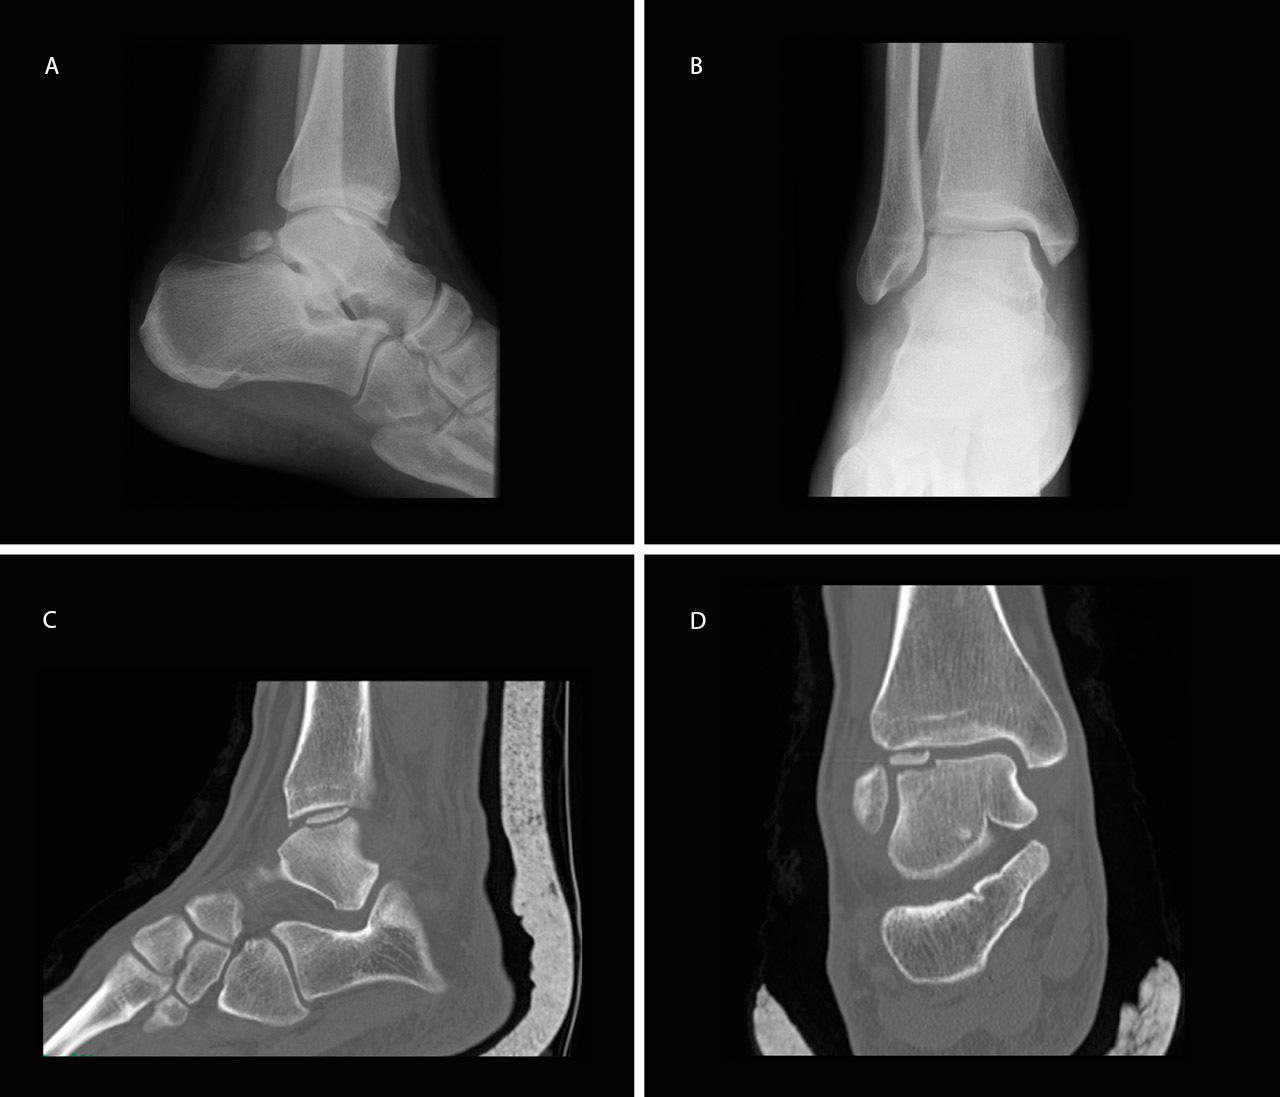

Se trata de un varón de 22 años de edad, atendido en urgencias por dolor en tobillo derecho tras mecanismo de supinación e inversión forzada en el tobillo derecho. Fue diagnosticado inicialmente de esguince de tobillo de grado II-III e inmovilizado con una férula suropédica durante 3 semanas. Inicialmente no se realizó ninguna prueba complementaria debido a que el paciente no cumplía los criterios de Ottawa. Cuando inició la deambulación, debido a la persistencia de dolor, tumefacción y limitación en la flexión dorsal del tobillo, a las 4 semanas se realizó una radiografía (Rx) en la que se observó un defecto óseo compatible con una LOT en la cúpula astragalina anteroexterna del tobillo (Figuras 1A y 1B). A los 5 días se realizó una tomografía computarizada (TC) que mostró una fractura osteocondral con fragmento de 1 cm2 volteado 180° (cartílago articular en contacto con hueso subcondral del talus), en la zona 3 de Elias(5)(Figuras 1C y 1D), por lo que se decidió realizar tratamiento quirúrgico.

El paciente se reincorporó a su actividad laboral (mozo de almacén) y deportiva a los 4 meses del accidente, sin dolor ni inestabilidad y con un rango de movilidad completo del tobillo. A los 6 meses se realizó una resonancia magnética (RM) que mostró la integración del fragmento, sin escalón articular ni signos de inestabilidad (Figura 3).